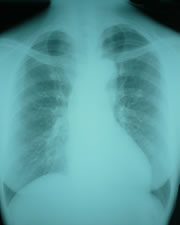

胸部レントゲン

ダイビングでリスクになる病気に、気腫性のう胞(ブラ)と肺気腫があります。これらは減圧性気胸(減圧時に起こる肺の気圧外傷、いわゆる肺破裂)の原因になります。